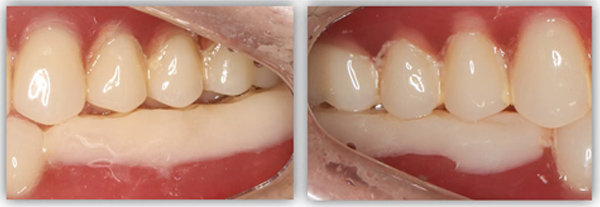

单颗是最常规的种植,不能因为常规就觉得简单,治疗时要追求小而精。从适应证把握到术式选择,再到修复方式,术后的结果有没有达到术前预期效果,都需要用心设计,事后复盘。这位患者是一位来自外地的年轻老师,有一颗6号牙需要种植。她只有在暑假两个月的时间内可以来院,希望能在暑假期间完成治疗。

为满足患者的需求,我为她制订了一个即拔即种、种植后早期负重的方案,把五个治疗步骤缩减为三步。首次来院时,我为她完成了拔牙、种牙和安装基台,6周后来院拆线和取模,两周后完成牙冠修复,也就是戴牙。整个治疗周期仅8周,不到两个月就完成了。

6号牙也就是第一磨牙,是最早萌出的恒牙,比较容易龋坏。它虽然不在前牙美学区,不太容易影响容貌,但出于对美学的高要求,我在设计方案时也考虑了是按常规流程先拔牙,再备洞,还是以修复为导向,先按现有的牙冠来确定未来修复体的形状,再去反推种植体植入的位置。后者对医生来说难度更高一些,但更有利于复原天然牙的形态。

为保证这个方案的顺利实施,我通过查阅文献去印证方案的可行性,还为她建议了适合的种植体,原来三个月的骨结合时间能缩短为两个月,种植体功不可没。